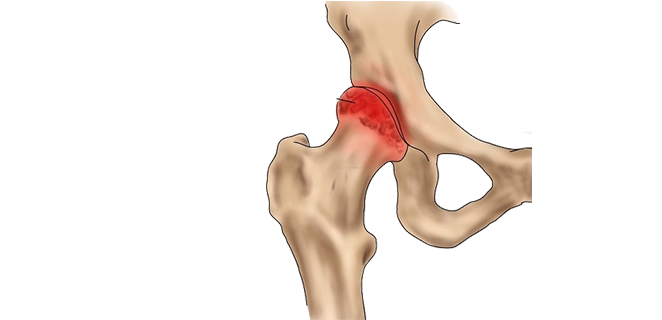

داء بيرتس

داء بيرتس هو مرض يصيب رأس عظمة الفخذ عند الأطفال